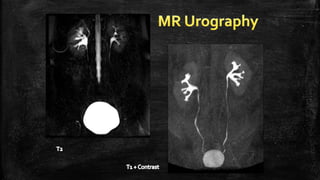

▪ TCC is much less common in the upper tract than in the bladder. However, it accounts for 90% of

all tumors that arise from the renal pelvic urothelium

▪ TCCs are typically isointense relative to the renal medulla onT1-weighted images, making the

detection of small tumors in the collecting system virtually impossible.

▪ Larger infiltrative tumors may obliterate the fat in the renal sinus, which may be appreciated on

T1-weighted images without the use of fat-saturation techniques.

▪ This appearance may mimic the so-called faceless kidney, described in the presence of a

duplicated collecting system.

▪ Coronal contrast-enhancedT1-weighted images are helpful in distinguishing between these two

conditions.

▪ Bright signal intensity due to urine in the collecting system onT2-weighted images provides

excellent soft-tissue contrast for the detection of these tumors, which are characteristically seen

as hypointense filling defects. InfiltrativeTCC can be seen on single-shotT2-weighted images as a

hypointense soft-tissue mass infiltrating the renal parenchyma, which has intermediate signal

intensitY.